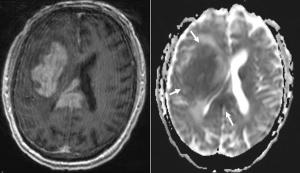

A 57-year-old woman with a history of stage IIB breast cancer (ypT2N1M0) status post neoadjuvant chemotherapy and left partial mastectomy presents to the radiation oncology clinic for CT simulation in preparation for breast radiotherapy. Noncontrast CT scan incidentally found the abnormality depicted with arrows below. What is your diagnosis?